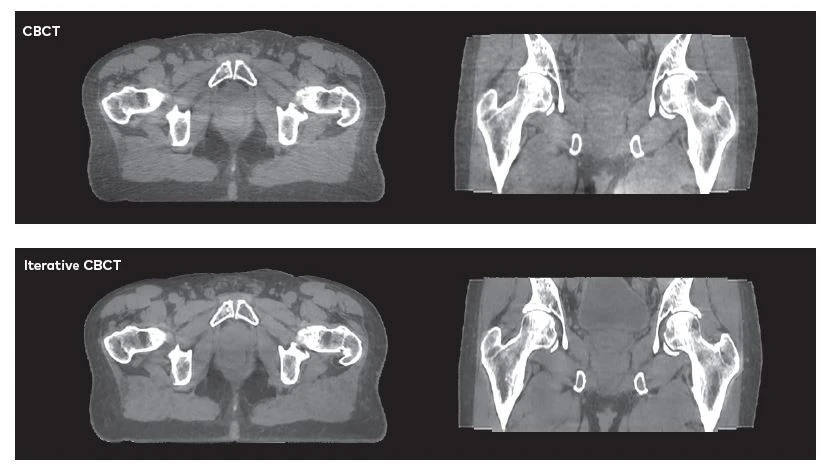

According to Eric Simmons, clinical marketing manager at Varian, iCBCT was developed with the goal of improving the image quality achieved with standard CBCT. Currently, CBCT is primarily used for bone and soft tissue matching during online setup correction at the start of a radiotherapy session. However, streaks, artifacts, scatter, and noise typically seen in standard CBCT scans can make them less useful. iCBCT images offer the sharpness and distinct soft tissue boundaries needed for improved image interpretation.

The greys for the bladder or prostate, and seminal vesicles are a lot more distinct from the blacks. They pop out more, and the whites are a lot sharper,” noted Hoang Tran, radiation therapist at St. Joseph Hospital. Currently, iCBCT is primarily used for scans of stationary anatomy such as the head, neck, and pelvis.

iCBCT allows better identification of anatomical structures that can be difficult or impossible to identify with a standard CBCT due to scan artifacts.  These artifacts can have many causes, from the presence of prostheses to tumor deformation from digestive gas.

When we scan a patient with an artificial hip or someone who has gas in the pelvic area, we see tremendous improvement in the visualization of anatomy with iCBCT compared to standard CBCT. You have to see it to appreciate it,” remarked Du.

“We had a patient with bilateral hip implants who was receiving treatment to his prostate and seminal vesicles,” said Seward. “We did an iCBCT scan and the images actually looked better than our CT-SIM scan because the artifacts were removed. We were able to visualize the prostate better than was possible during the planning process. We actually took the iCBCT image and registered it to our planning CT to confirm that the dose was being delivered to the correct location.”